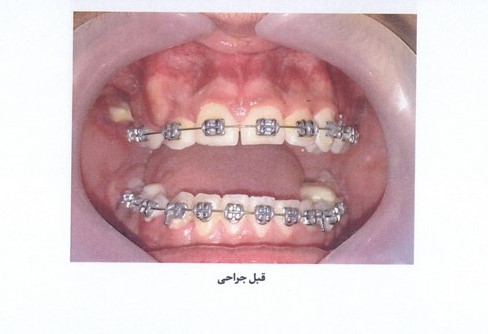

اکسپوز دندان کانین نهفته توسط لیزر دایود نکته بسیار مهم در اکسپوز دندان نهفته کانین توسط لیزر این است که جهت Tip لیزر به صورت عمود بر دندان نباشد؛ به دلیل جذب لیزر در هموگلوبین و احتمال نکروز دندان... -